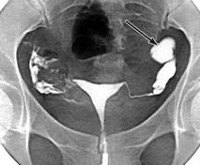

• УЗИ тазовых органов. Между яичниками и маткой определяется объемная жидкостная структура. Складки маточных труб сглажены или отсутствуют.

• Гистеросальпингография. При постоянном варианте болезни контрастное вещество не поступает в одну или обе трубы и скапливается в матке. При вентильном сактосальпинксе пораженная труба определяется как расширенная, колбообразная.